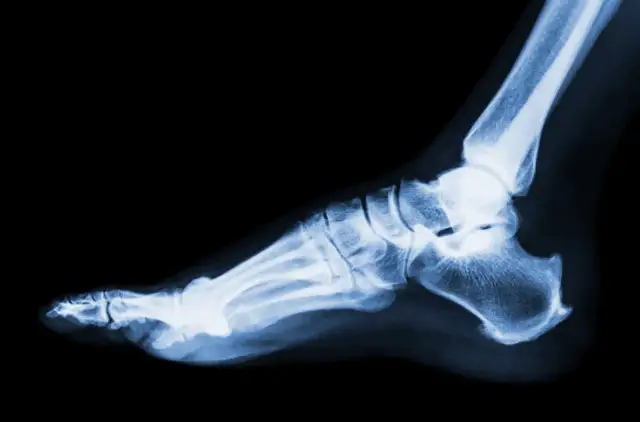

Poznaj kluczowe objawy skręcenia stawu skokowego: ból, obrzęk, niestabilność. Dowiedz się, jak rozpoznać uraz i co robić, by szybko wrócić do zdrowia.

Sprawdź, jak wygląda skręcona kostka: objawy, opuchlizna, krwiak i stopnie urazu. Dowiedz się, jak rozpoznać skręcenie i kiedy szukać pomocy lekarskiej.

Poznaj objawy skręconej kostki, jej stopnie i skuteczną pierwszą pomoc. Dowiedz się, kiedy potrzebujesz lekarza i jak uniknąć powikłań.